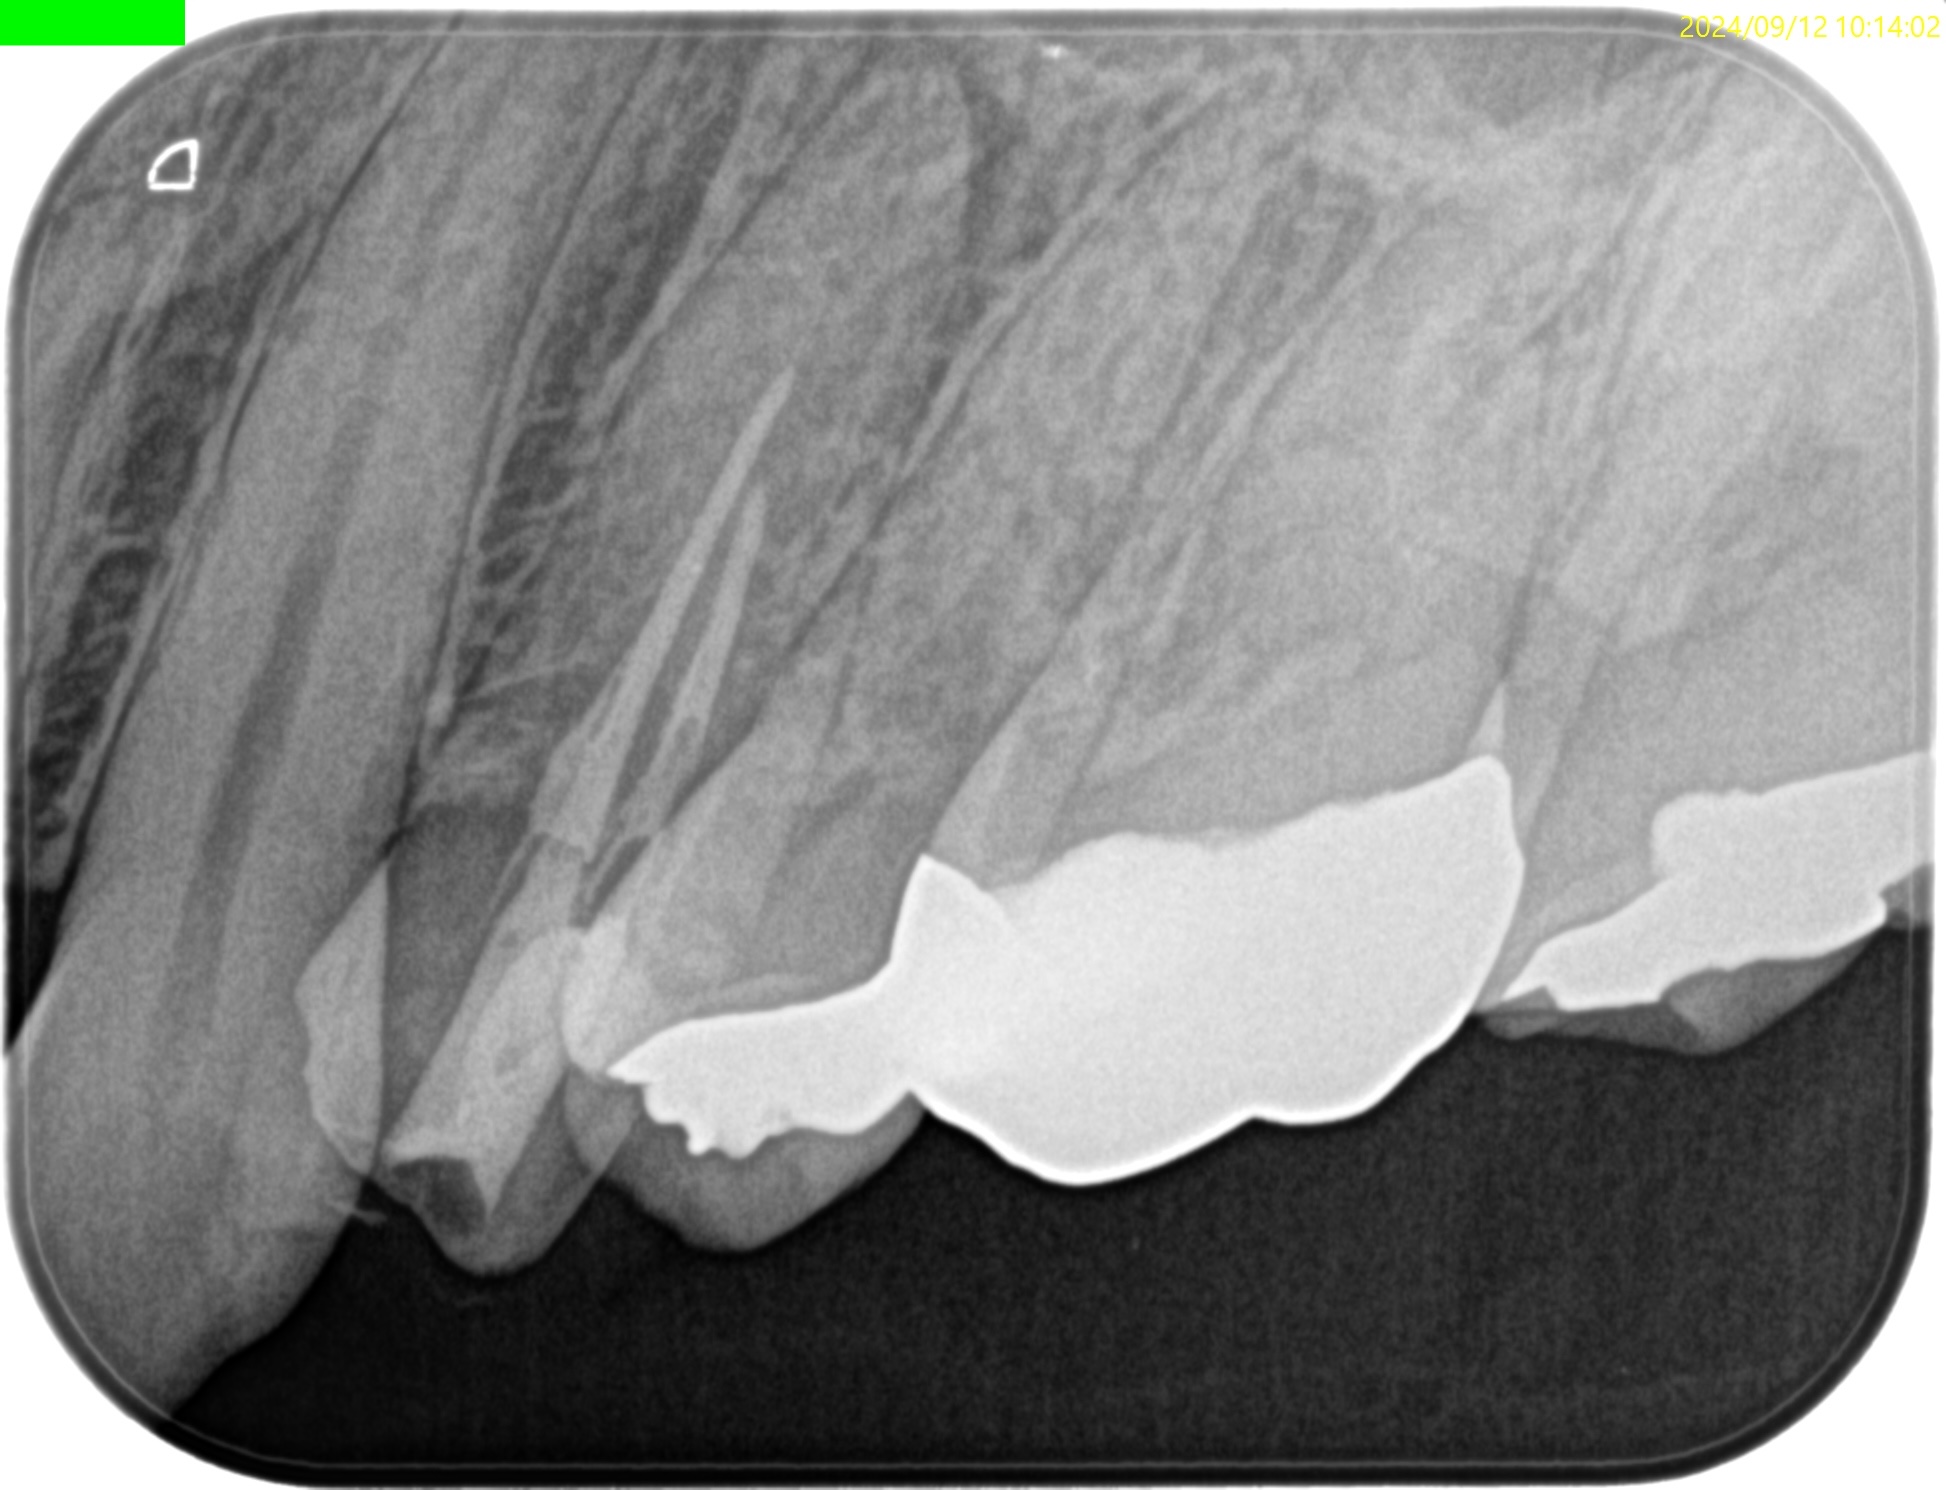

術後にPA, CBCTを撮影した。

#12 Apicoectomy 1yr recall(2026.2.27)

1年前と比較した。

問題は解決した。